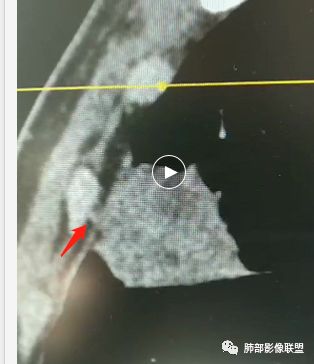

甄德强:这个是炎症,治疗一月后复查图片。

Coke with ice:薄层很重要,要不然好多征象都是靠感觉。